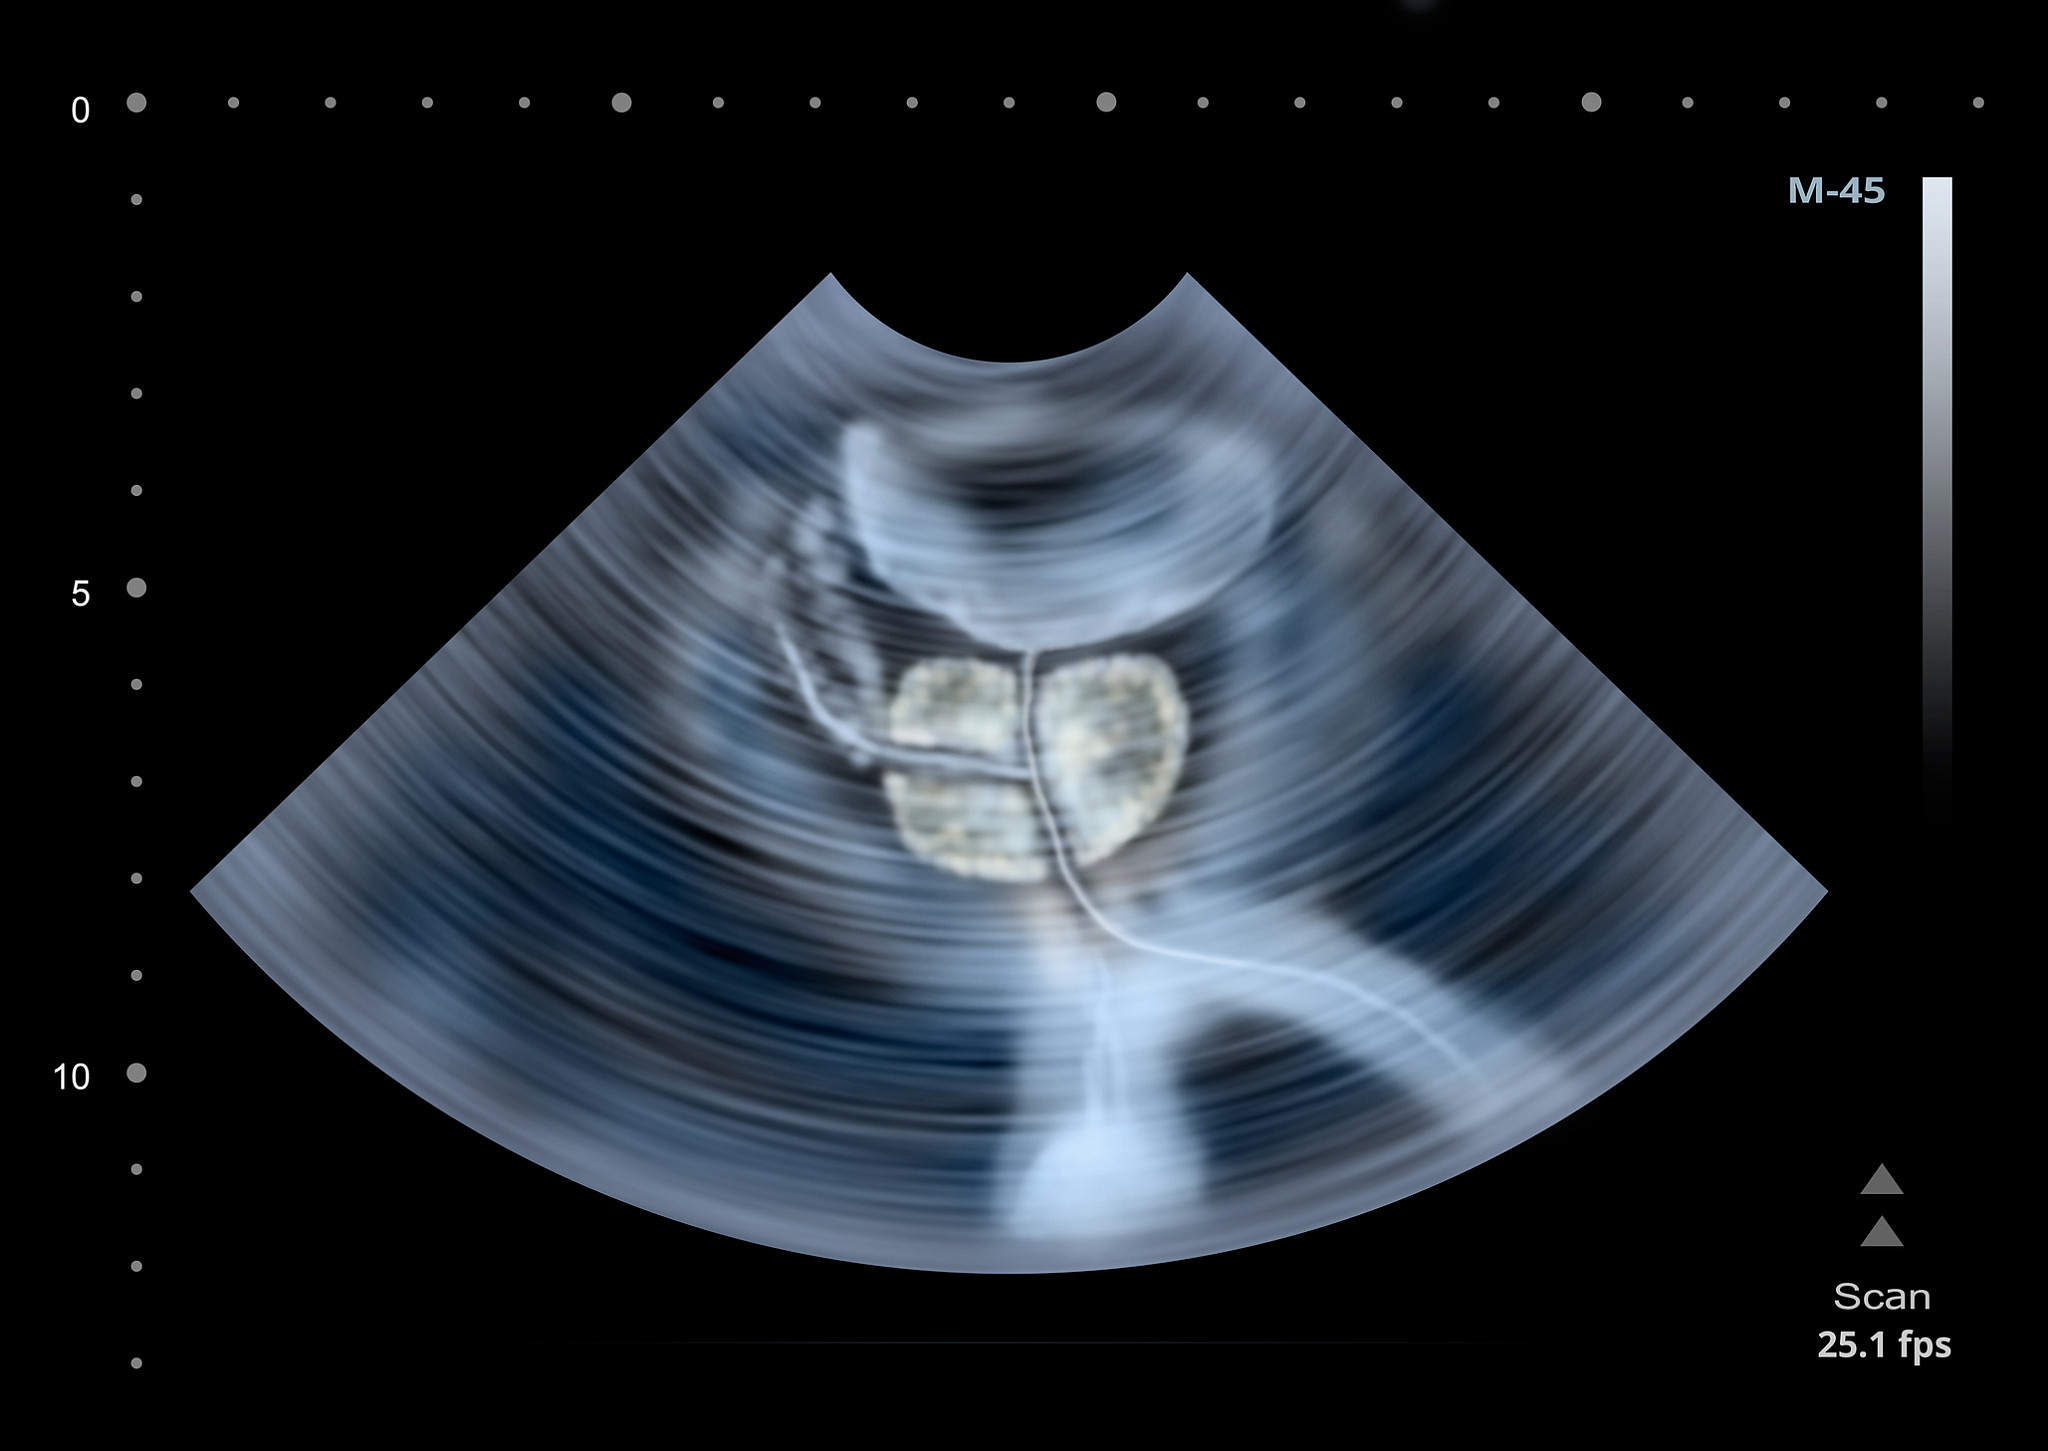

Gelişmiş tanı yöntemlerinin kullanılarak, tedaviden önce hastalığın en doğru tanımı yapılmaktadır.